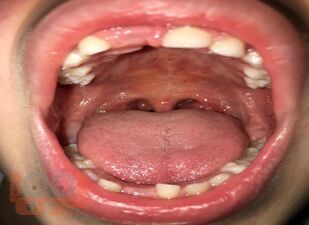

В учебном пособии представлены дифференциально-диагностические признаки проявлений коронавирусной инфекции от основных заболеваний слизистой оболочки рта, позволяющие врачу-стоматологу систематизировать полученные знания.

Пособие предназначено для врачей-стоматологов разных специальностей: терапевтов, ортодонтов, общей практики, хирургов, ортопедов. Пособие может быть использовано для подготовки к аккредитации врачей по специальности «Стоматология терапевтическая», а также врачами ординаторами как дополнительная учебная литература.